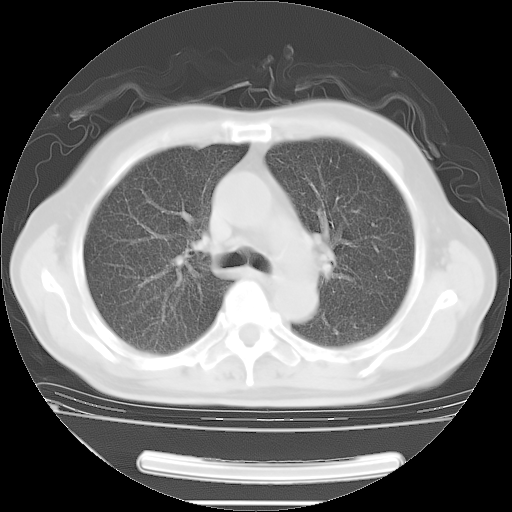

今天复查肺部CT,发现双肺广泛磨玻璃样改变。所以我把3月19日和5月9日相隔50天的肺部CT上传。请大家会诊。

2009年3月19日肺部CT片。

2009年3月19日肺部CT

大致读了系列胸部CT:纵隔窗无明显异常,肺窗:从4、27至今:主要是双肺中下野外带可见毛玻璃样改变,目前处于急性肺泡炎阶段,至于原因考虑1、结替组织或胶原血管性疾病所致?2、恶性疾病如恶组在肺部所致的表现或细支气管肺泡癌?3、药物或其它原因如肺蛋白沉着症所致肺泡炎目前不太可能?总之,明天就去请我院的呼吸科、感染科、血液科和临免专家会诊哈。